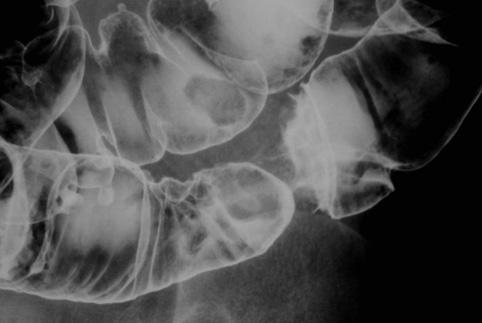

Cáncer del Colon motivado por Ileus con Pólipo incrustado

[Image-ID:10185]

Tumor Epitelial Maligno/Adenocarcinoma

colon/sigmoides

Rayos X

Tipo 1(Tipo protuído)/

30 - 34

s(a)

presente(simultáneo)